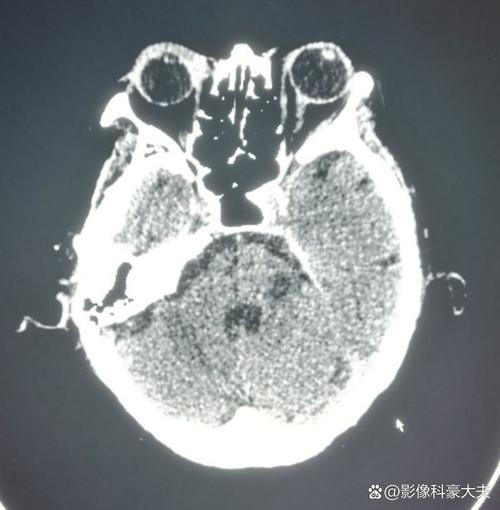

- 发病24小时后:这是脑CT诊断脑梗死最敏感的时期之一,梗死灶的低密度改变会非常清晰、明确,边界也比较清楚,很容易被诊断出来。

- 排除其他疾病:这是脑CT在急性卒中中的首要作用,当患者出现中风症状时,医生首先要做的是排除脑出血,脑出血在CT上表现为高密度影,非常清晰,如果CT显示有出血,那么就不能使用溶栓药物(如阿替普酶),治疗方案将完全不同,CT是决定下一步治疗的关键“分水岭”。

(这是一个示意图,左侧为早期CT可能正常,右侧为24小时后CT显示的低密度梗死灶)